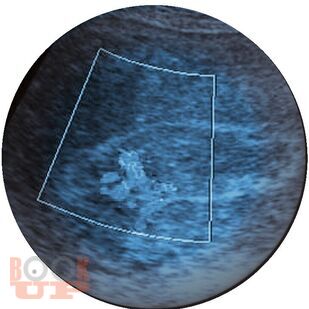

В руководстве проанализированы данные литературы по вопросам физиологического и патологического течения послеродового периода и представлены результаты собственных исследований. Подробно рассмотрены инфекционные осложнения в пуэрперии, в том числе и в послеоперационном периоде. Дана общая характеристика госпитальных инфекций в акушерском стационаре на современном этапе с освещением вопросов этиологии и микробной резистентности. Особое внимание уделено фоновым заболеваниям, которые способствуют развитию гнойно-воспалительных осложнений у родильниц и новорожденных. Детально изложены общие принципы диагностики и лечения неинфекционных осложнений пуэрперия.

Руководство предназначено для акушеров-гинекологов, преподавателей системы последипломного образования, преподавателей вузов, врачей ультразвуковой диагностики, инфекционистов, клинических ординаторов и интернов.